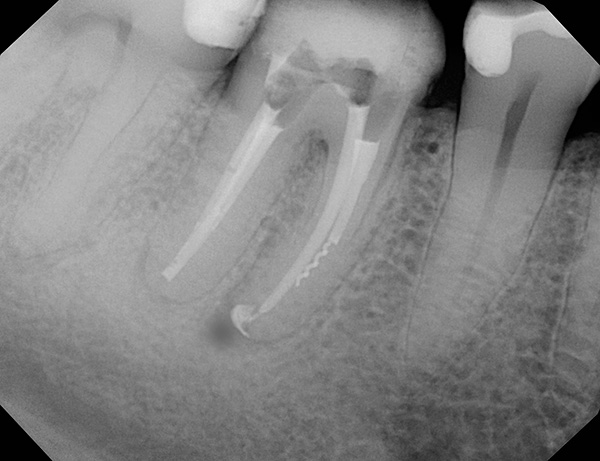

A imagem abaixo mostra um dente do siso retardado:

Da prática do dentista

Alguns dentistas de orçamento (especialmente em pequenas cidades e vilarejos) que trabalham em visitas mistas (terapia e cirurgia) têm medo de remover os dentes dessa categoria. Vendo um dente semi-refinado ou, principalmente, refinado (da figura), eles podem imediatamente se recusar a ser removidos e enviar o paciente à cirurgia maxilofacial para a clínica regional ou centro odontológico mais próximo. A motivação para isso pode ser tanto a relutância em se preocupar com esses dentes (pode levar 1-2 horas de trabalho meticuloso para o procedimento) quanto o medo de que a falta de experiência e ferramentas não permita remover todas as raízes - o que significa que você ainda precisará enviar o paciente atormentado para outro dentista mais qualificado nesta matéria.